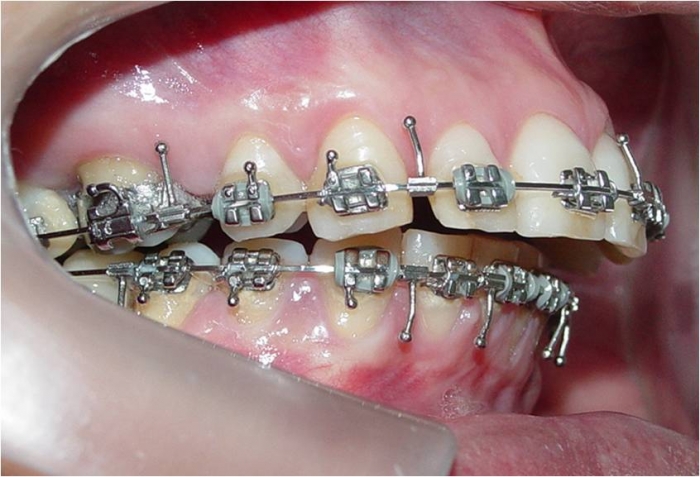

Mordida final